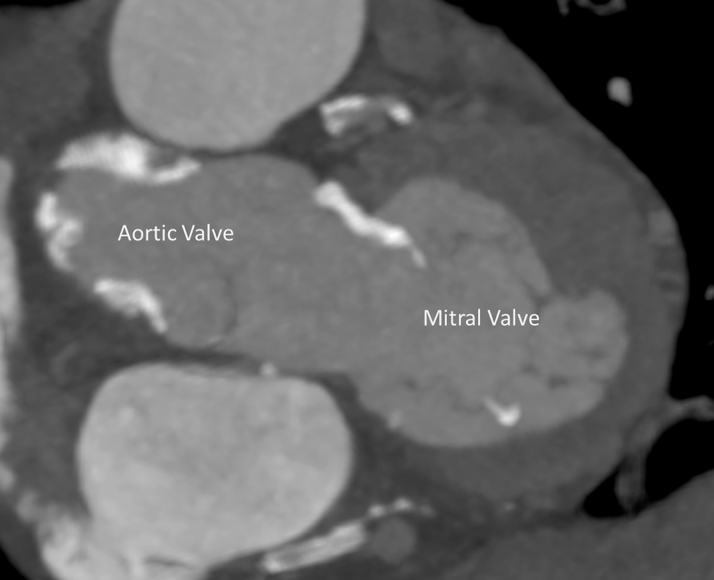

Echocardiography showed severe functional MR with a restricted and short posterior leaflet (MR ERO 0.11 cm2, dPmean 2 mm Hg). The aortic valve displayed severe insufficiency and mild stenosis. Multislice computed tomography (CT) imaging proved a suitable aortic valve anatomy for TAVR (perimeter 7.9 cm, diameter 25.2 mm, area 476 mm2, adequate coronary distance). Analysis of the mitral valve showed an ample estimated neo left ventricular outflow tract (>320 mm2 in systole and >400 mm2 in diastole) (Figure 1), an anterior-posterior distance of 31 mm, and an intercommisural distance of 42 mm allowing for approximately 15% oversizing using the 35M low-profile Tendyne valve. Simulation of TAVR implantation was not included. According to the scoring system proposed by Guerrero et al. (1), the patient had a MAC score of 3, mild calcification, most prominently with a sporn on the anterior-medial trigone (Figure 2). The suggested left ventricular apical access point for the TMVR deviated only 1 cm from the usual transapical TAVR access point, suggesting a favorable access for both the TMVR and the TAVR (Figure 3). Patient consent for publication of this case was obtained.

Figure 2.

Mitral Valve Calcification